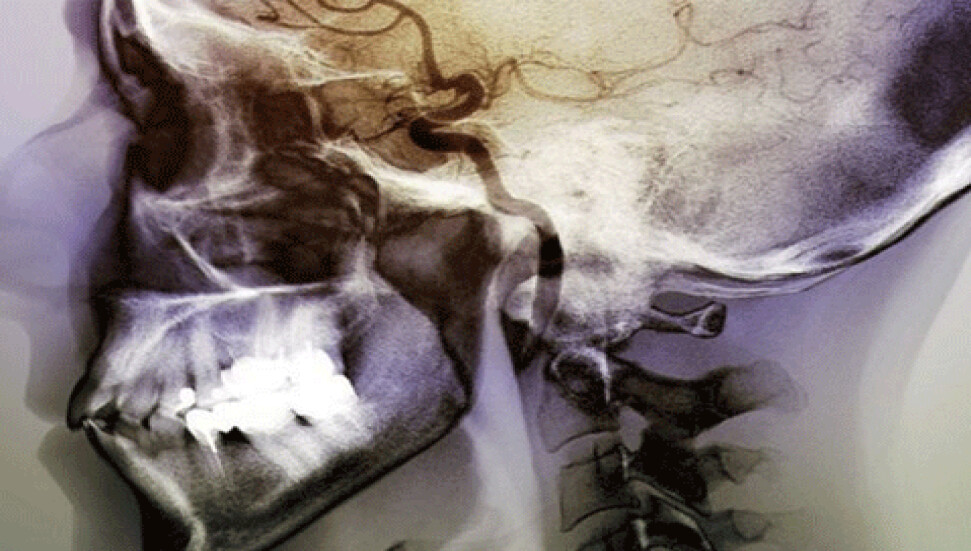

Felç sonucu beynin iç kısmındaki insular korteks bölgesi zarar görenlerin sigarayı daha kolay bıraktığını tespit eden uzmanlar, beynin belirli bir bölgesinin sigara tiryakiliğinde itici güç olduğu sonucuna vardı.

ABD'deki Rochester Üniversitesi'nde yapılan araştırmada farklı beyin hasarına uğramış 156 felç hastası incelendi.

İnceleme sonucu, felç geçirdiklerinde insular korteks bölgesi zarar gören hastaların sigarayı daha kolay bıraktıkları saptandı.

Beyin taraması sonucu deneklerin 38'inde insular kortekste, 118'inin de beynin diğer bölümlerinde hasar oluştuğu tespit edildi.

İnsular korteksi zarar görenlerin yüzde 70 oranında sigarayı bıraktıkları görülürken, beynin diğer kısımları zarar gören hastaların sigarayı bırakma oranı yüzde 37'de kaldı.

Beynin derinliklerinde iyi korunan bir bölgede olan insularr korteks, beynin diğer bölgeleriyle yoğun bağlantılara sahip. Uzmanlar bu bölgenin arzular ve duygularla ilgili olduğuna inanıyor.